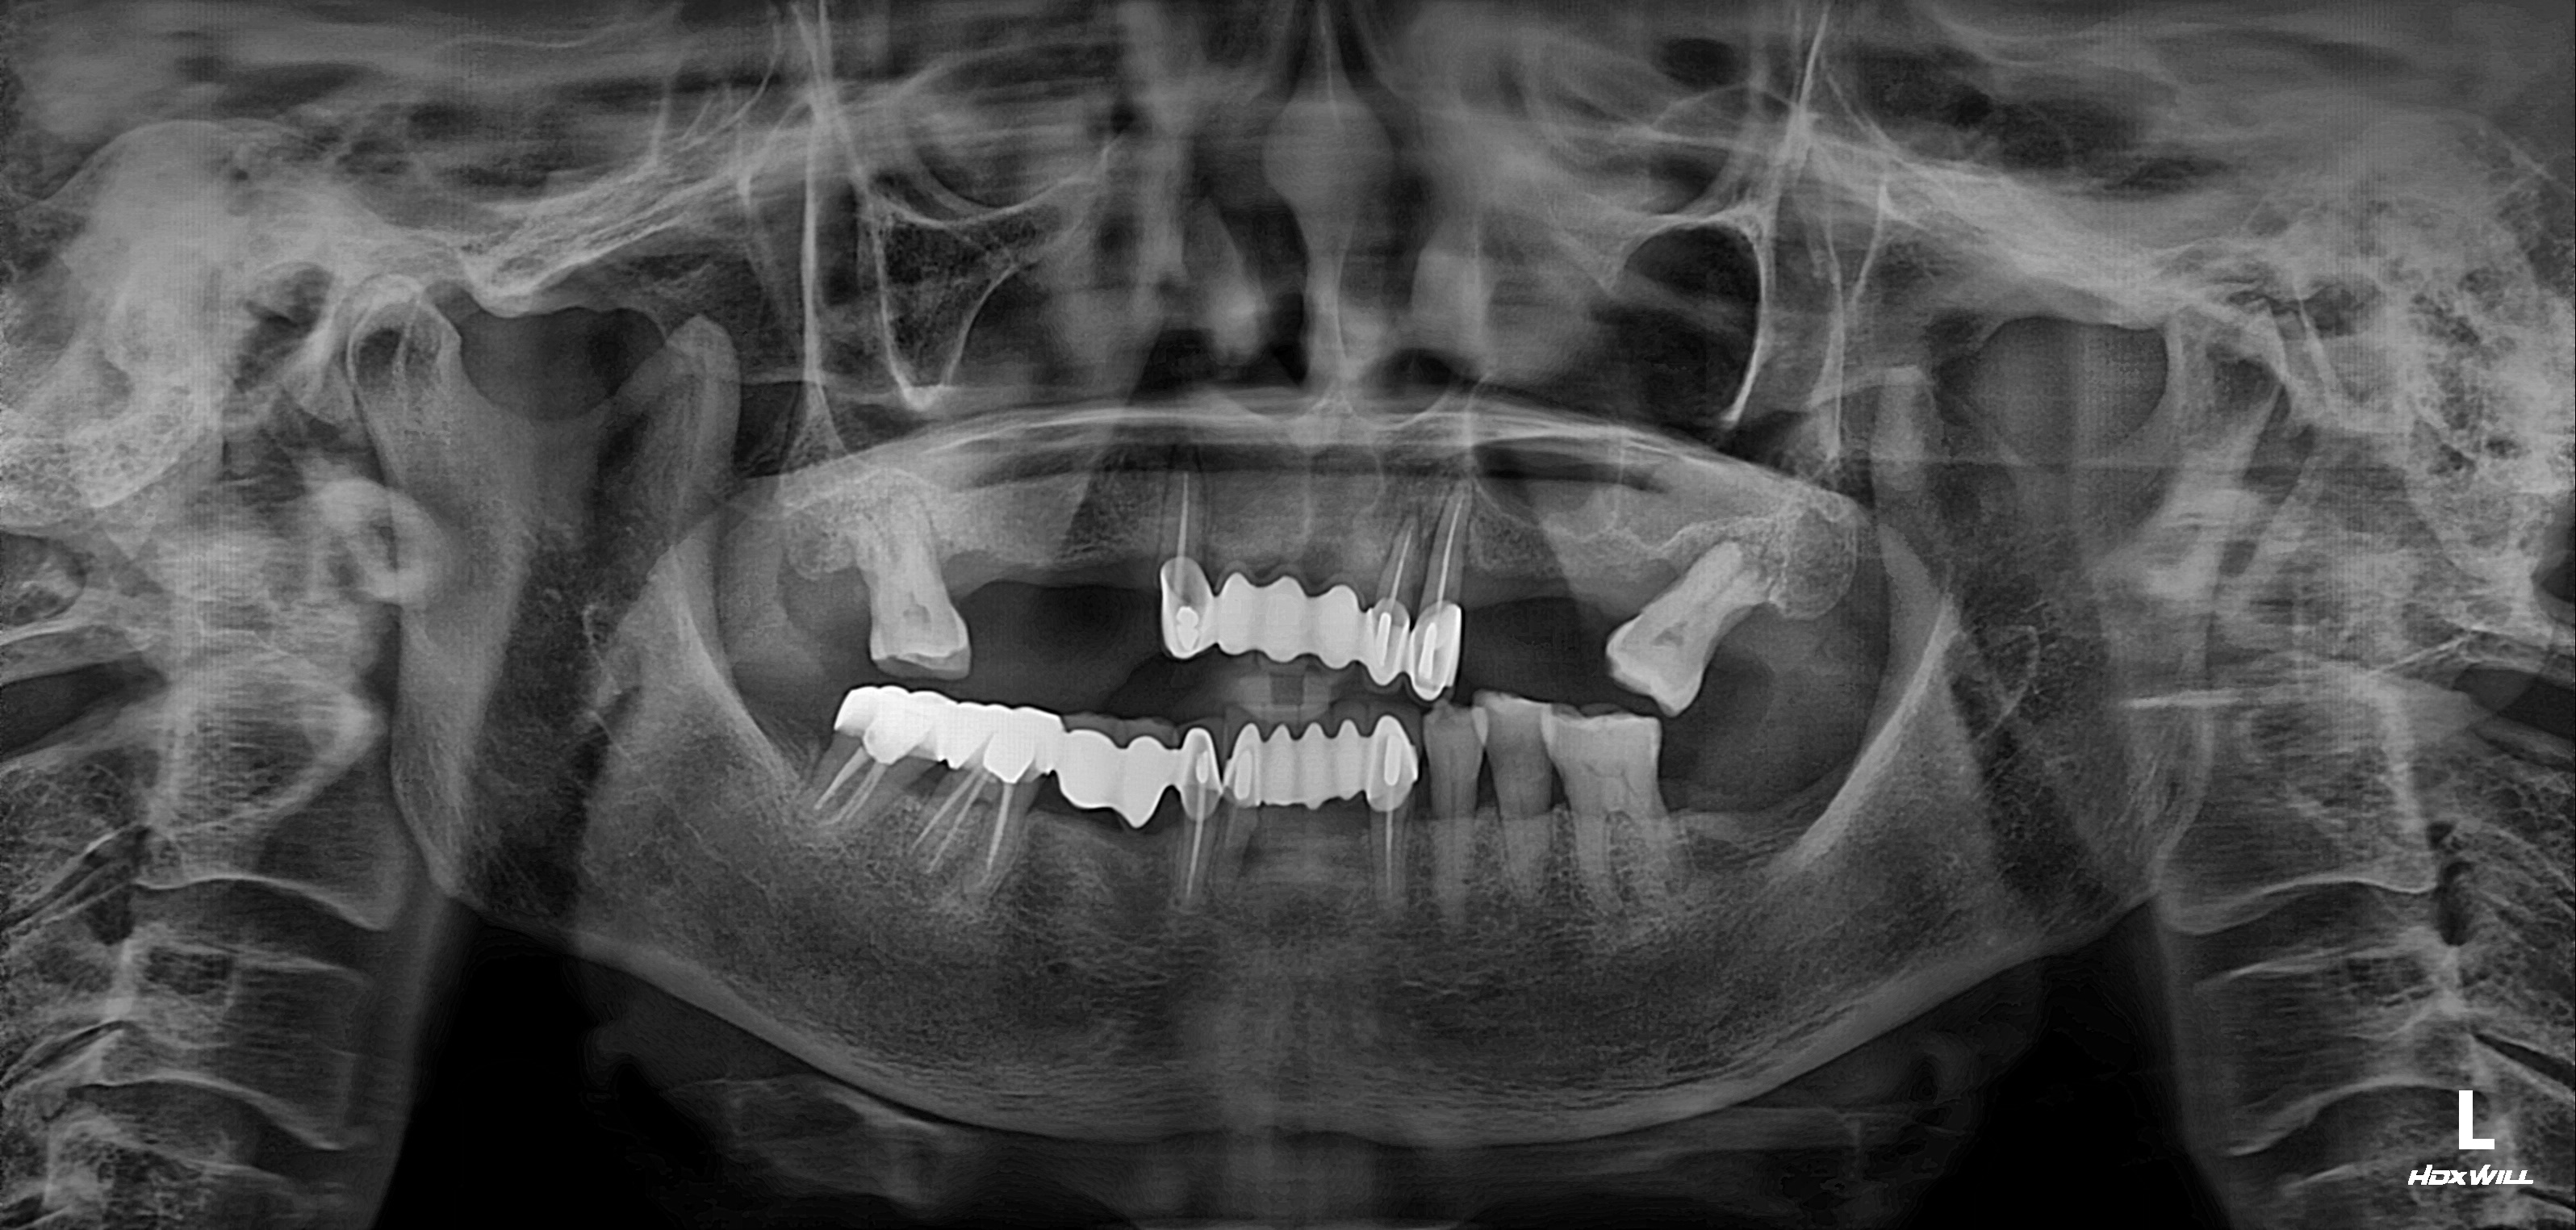

수술 전

수술 후

구치부 임플란트 식립사례

전후사진